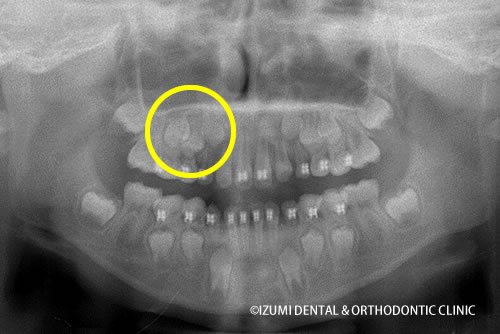

それから、約1年半、治療を行い、子供の矯正が終了しました。

矯正終了時(8歳11ヶ月)

顎骨の比較

顎は大きくなり、歯の並び方が自然なカーブに変わっていったのがおわかりになるでしょう。

顎が大きくなり緩やかなカーブに変化したことで、ある程度は、自分の場所を確保した永久歯がホッとしているように感じられます。

しかし、○で囲った場所のように永久歯はごちゃごちゃと塊で存在し、綺麗に並んで萌出するのは難しいだろうと予想されます。

このような場合は、永久歯が萌出した後、歯列矯正を行なっていきます。